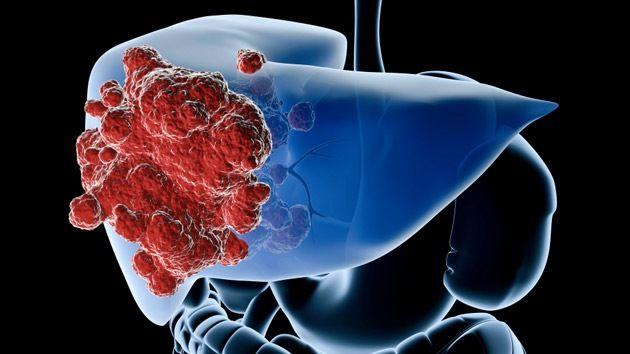

En 2030, el hígado graso causará más cáncer de hígado que la hepatitis

El cáncer de hígado es el quinto tipo de tumor más frecuente en el mundo y si no se lo detecta a tiempo, su abordaje se torna más complejo. Su incidencia se triplicó en los últimos 35 años y, a nivel mundial, se...